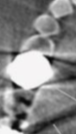

undersampling/moire

what do you call the artifact seen here that causes alternating light and dark lines (not the metal)